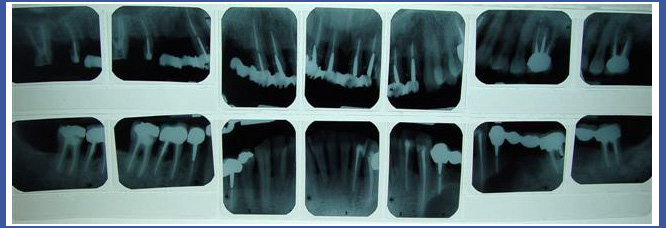

3.צילום סטטוס:

זהו צילום שנעשה במכון רנטגן וכולל 14-18 צילומים פריאפיקלים המכילים את כל השיניים בפה.

צילום סטטוס נעשה בדרך כלל כאמצעי אבחנתי לאנשים שעוברים\עברו טיפול שיקומי בפה, אנשים שיש להם בעיית נסיגת עצם והחניכיים –הצילום מאפשר לראות את גובה העצם המאחזת את השיניים.

במקרים רבים רופא השיניים יבקש מכם להביא צילום סטטוס הכולל גם צילומי נשך בערכה אחת.

4. צילום סטטוס מקביליות:

במקרים רבים רופא השיניים יפנה אותך לבצע צילום "סטטוס מקביליות" . ובכן זהו בעצם הדבר האמיתי ולא צילום הסטטוס הרגיל..

הצילום בנוי מ 20 צילומים פריאפיקלים (בודדים), כאשר לצילום זה יצורפו תמיד גם 4 צילומי נשך.

בצילום זה משתמשים בפילים צר יותר לשיניים קדמיות ובכל צילום מתמקדים בשן אחת בלבד, בניגוד לסטטוס רגיל שבפילים אחד מתמקדים בכמה שיניים במקביל.

בצילום סטטוס מקביליות, הצילום עצמו מוחזק בפה באמצעות מכשור פלסטי נקי ,אסתטי וברוב המקרים אף סטרילי. הקרן ממוקדת ואינה מתפשטת לצדדים.

הצילום קרוי בשפה מקצועית "אורתורדיאלי" והוא בעצם כמו "צל" של השן , אמנם מוגדל אך ביחס דומה.

דמיינו עצמכם עומדים מול מראה בצורה ישרה ומה יקרה אם נטה את המראה לפנים או לאחור ?ודאי נראה חלקים בגוף מעווותים, רגליים קצרות, גוף ארוך וכו'. זהו בעצם ההבדל בין צילום סטטוס רגיל לבין צילום סטטוס מקביליות שעשוי נכון ומדוייק.

רופאי שיניים נוטים להפנות מתרפאים לבצע צילום סטטוס רגיל, כיוון שהתמונה המתקבלת סבירה לצרכים שיקומיים, קוסמטיים וכירורגיים בסיסיים ולומר את האמת, גם הם אינם מודעים תמיד היטב לחסרונותיו של צילום זה.

אמנם צילום סטטוס מקביליות יקר יותר, אך לדעתי ההשקעה שווה ללא כל ספק.